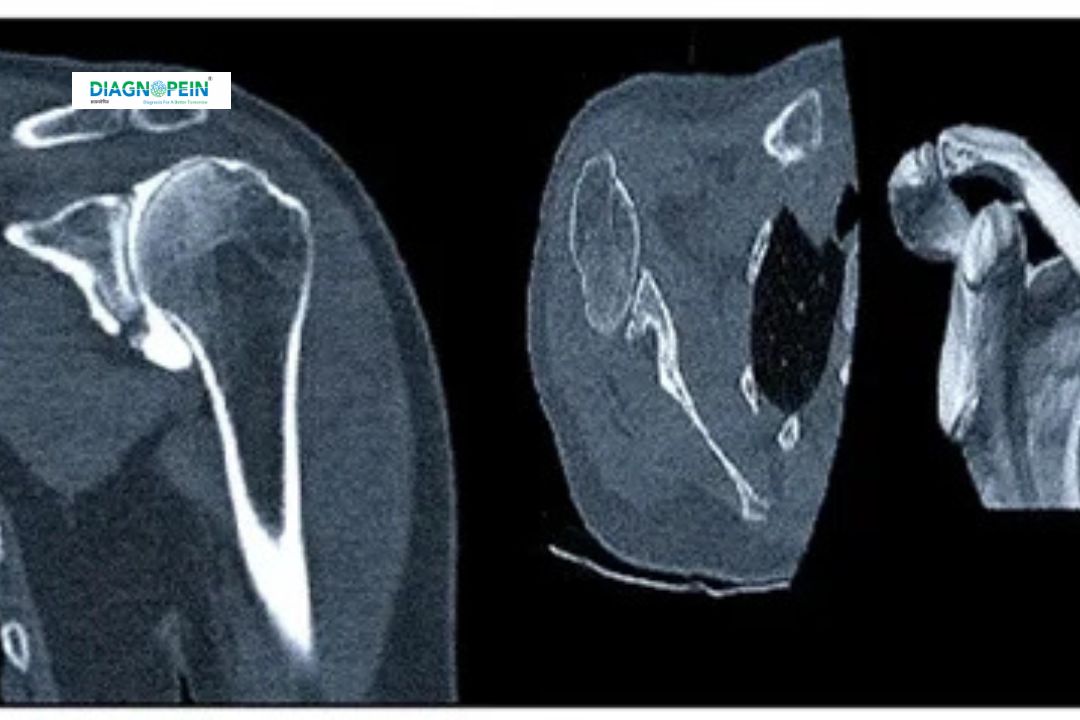

The CT RT Shoulder Joint (Plain) is a detailed imaging procedure that captures cross-sectional images of the right shoulder joint without using contrast dye. It uses advanced Computed Tomography (CT) technology to create precise images of bones, muscles, ligaments, and joint structures. This scan helps doctors identify shoulder fractures, joint irregularities, dislocations, arthritis, and bone tumors.

The shoulder joint is one of the body’s most mobile and complex joints, making it prone to various injuries and degenerative conditions. A CT RT Shoulder Joint (Plain) scan offers critical diagnostic insights that cannot be obtained through standard X-rays.

2. High-resolution imaging: Produces 3D views of the bone structure for accurate diagnosis.

5. Detects subtle abnormalities: Identifies even small fractures and microcalcifications not visible in X-rays.